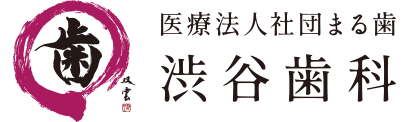

1. マウスピース

歯ぎしりや食いしばりの原因は不明な事が多く、確実にやめる事は困難です。しかしそのままにしておくと、歯や顎に悪い影響を与えてしまうため、歯科医院でマウスピース(ナイ トガード)を作製することをおすすめします。 マウスピースをつけることで歯と歯の間にクッションを設け、直接歯にかかる力を逃がし、歯が傷つけられるのを防ぎます。 歯ぎしりの大きな原因は日常生活におけるストレスだと言われており、患者自身が日常で抱えるストレスを減らさなければ症状の改善が見込めない可能性があります。注意点

- 基本的には就寝中に装着するものであり、過剰な力の方は穴が開いてしまうことさえあります。

- マウスピースもかみ合わせの調整は必要で、間違ったかみ合わせのままで装着してはあまり効果がありません。市販のものですとかみ合わせに調整がきかないため、かえってご自身のかみ合わせを悪くしてしまいます。 きちんと歯医者に行って、自分の歯型に合ったマウスピースを作製し装着するようにしましょう。